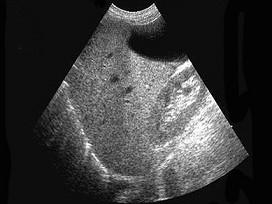

下列图像最可能的诊断是 ( )A.脂肪肝B.肝囊肿C.肝血管瘤D.原发性肝癌E.肝炎肝硬化

问题 下列图像最可能的诊断是 ( )

选项 A.脂肪肝 B.肝囊肿 C.肝血管瘤 D.原发性肝癌 E.肝炎肝硬化

答案 A